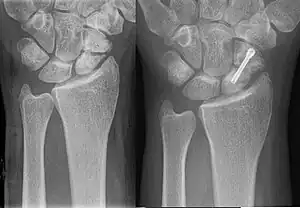

Fijación

Para estabilizar los fragmentos del hueso fracturado se utilizan placas de metal, pernos, tornillos y varillas, que pueden ser atornillados o colocados en el interior del hueso.